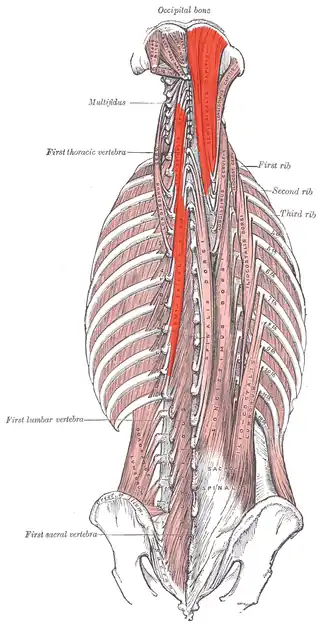

Muscle semi-épineux

Muscle semi-épineux

Les muscles semi-épineux :

En haut à droite le muscle semi-épineux de la tête.

A gauche le muscle semi-épineux du cou et le muscle semi épineux du thorax.| Groupe | |

Les muscles semi-épineux (ou muscles demi-épineux selon l'ancienne terminologie) sont des muscles pairs du dos situé profondément dans les gouttières vertébrales.

Les muscles semi-épineux font partie des muscles transversaires épineux.

Ils sont constitués de trois muscles :

Les muscles semi-épineux

Les muscles semi-épineux Détail du muscle semi-épineux du thorax

Détail du muscle semi-épineux du thorax Les muscles semi-épineux du thorax

Les muscles semi-épineux du thorax Les muscles semi-épineux de la tête

Les muscles semi-épineux de la tête